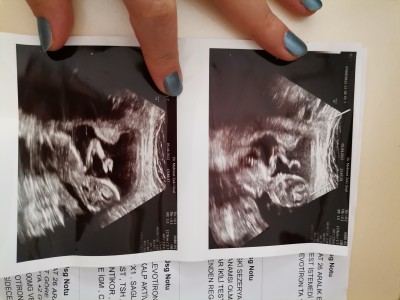

kızlar 14. Haftam doktor erkek dedi kesin sizce tahmininiz varmı değişirmi acaba yanılma olabilirmi

Gebelik haftası 14-1